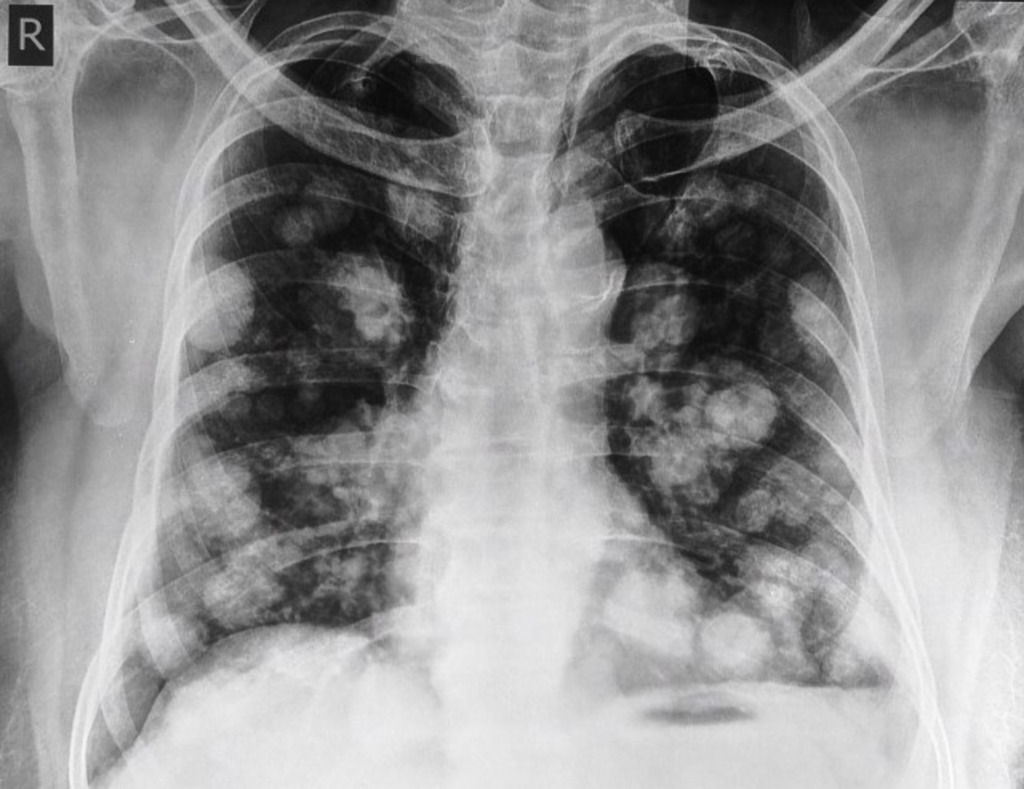

Example 3

Diagnosis

Cannonball metastases